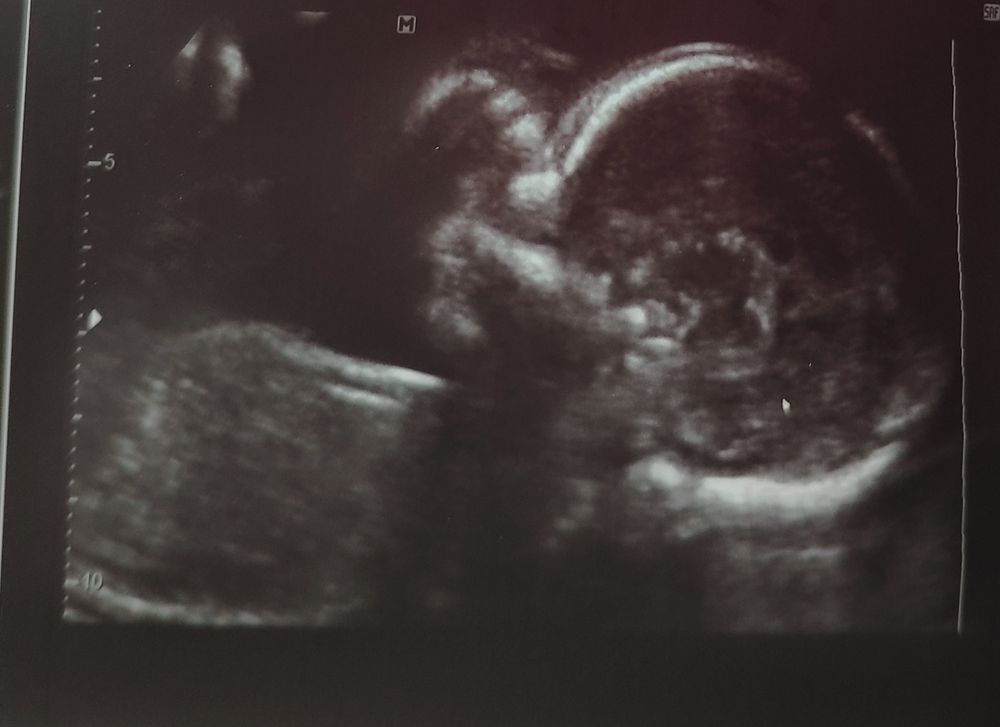

Второй скрининг

Кто бы там не был, определенно очень красивый малышочек там сидит 🥰😻🤗

Мои поздравления🎉🎊 самое главное, что все хорошо👍 я тоже вижу тут мальчика. Как говорила моя узистаа, что мальчики на таких сроках более лобастые. Напишите пожалуйста потом как узнаете пол)) я бы не выдержала и уже взорвала конверт 😆

Поздравляю вас с хорошим скринингом. Мне почему-то на фотке тоже мальчик представляется.

Mi Mi, мы узнаем кто у нас на следующих выходных.....мне все-равно кто будет,но хочется платьев и бантов 😂А смотрю на фото и понимаю,что это сыночек))))Хотя посмотрела фото УЗИ в интернете,не всегда похожи)))